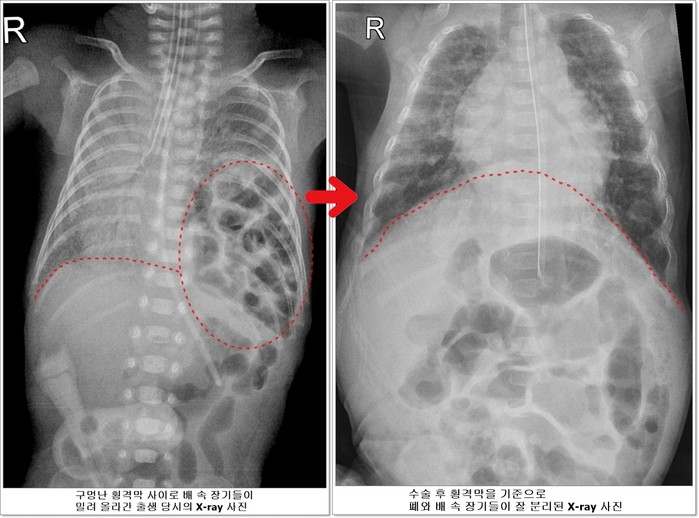

선천성 횡격막 탈장증이란 가슴 안의 심장과 폐를 배 속의 소화기 장기들로부터 분리해주는 횡격막에 선천적으로 구멍이 나는 질환이다. 배 속의 장기가 횡격막의 구멍을 통해 밀려 올라와 가슴안의 심장과 폐를 압박해 폐가 제대로 펴지지 않아 호흡곤란이 오고 심장기능 또한 떨어지게 된다.

![]() |

| ▲전호삼 아기의 치료 전 후 X-ray사진 비교 |